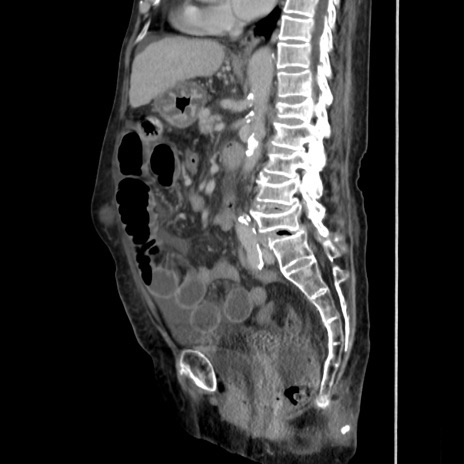

症例31(矢状断像)

【症例】80歳代 女性

【主訴】腹部膨満感

【現病歴】他院にて肝硬変にてフォロー中。1週間前から便秘、腹部膨満感、臍部腫瘤あり受診となる。

【既往歴】肝硬変

【身体所見】腹部膨隆あり、皮膚変化なし、疼痛なし。

【データ】WBC 4600、CRP 0.25